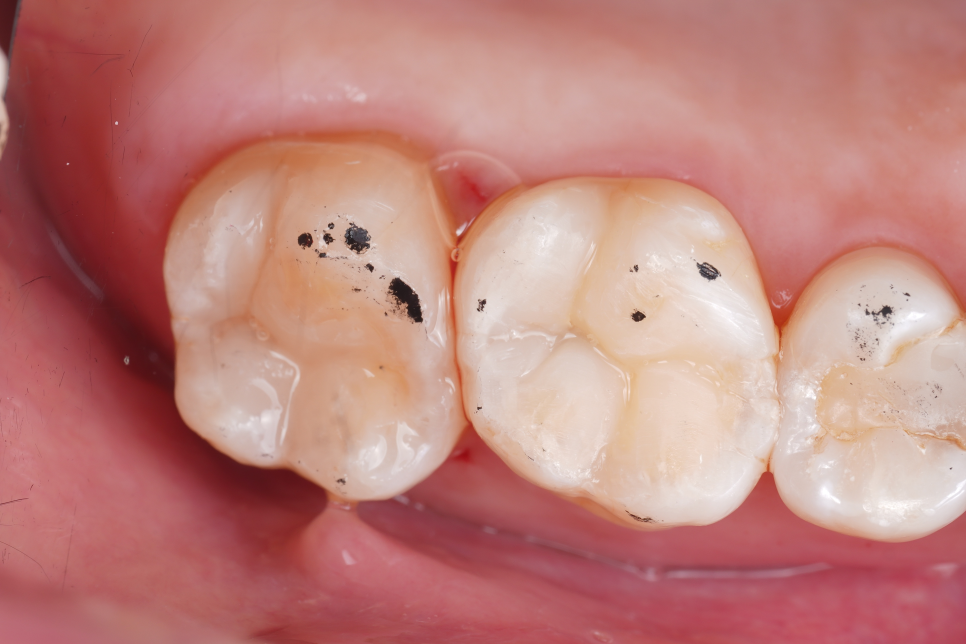

이렇게 진단이 정확해지면 과정도 달라져요. 충치가 있는 부분만 제거하고 건강한 치질은 그대로 남길 수 있게 되거든요.

이 경험이 쌓이면 자연스럽게 이런 변화가 생깁니다. 예전 같으면 신경치료까지 진행됐을 치아가 레진만으로 마무리되는 경우가 꽤 생깁니다.

실제로도 타 치과에서 신경치료 진단을 받고 오셨던 분들 중에서 큐레이로 다시 확인해 보고 최소 침습 레진으로 마무리된 케이스도 적지 않아요.

환자분 입장에서는 치아를 하나 더 살린 셈이죠ㅎㅎ

레진으로 티 안 나게 채워드렸어요👏🏻